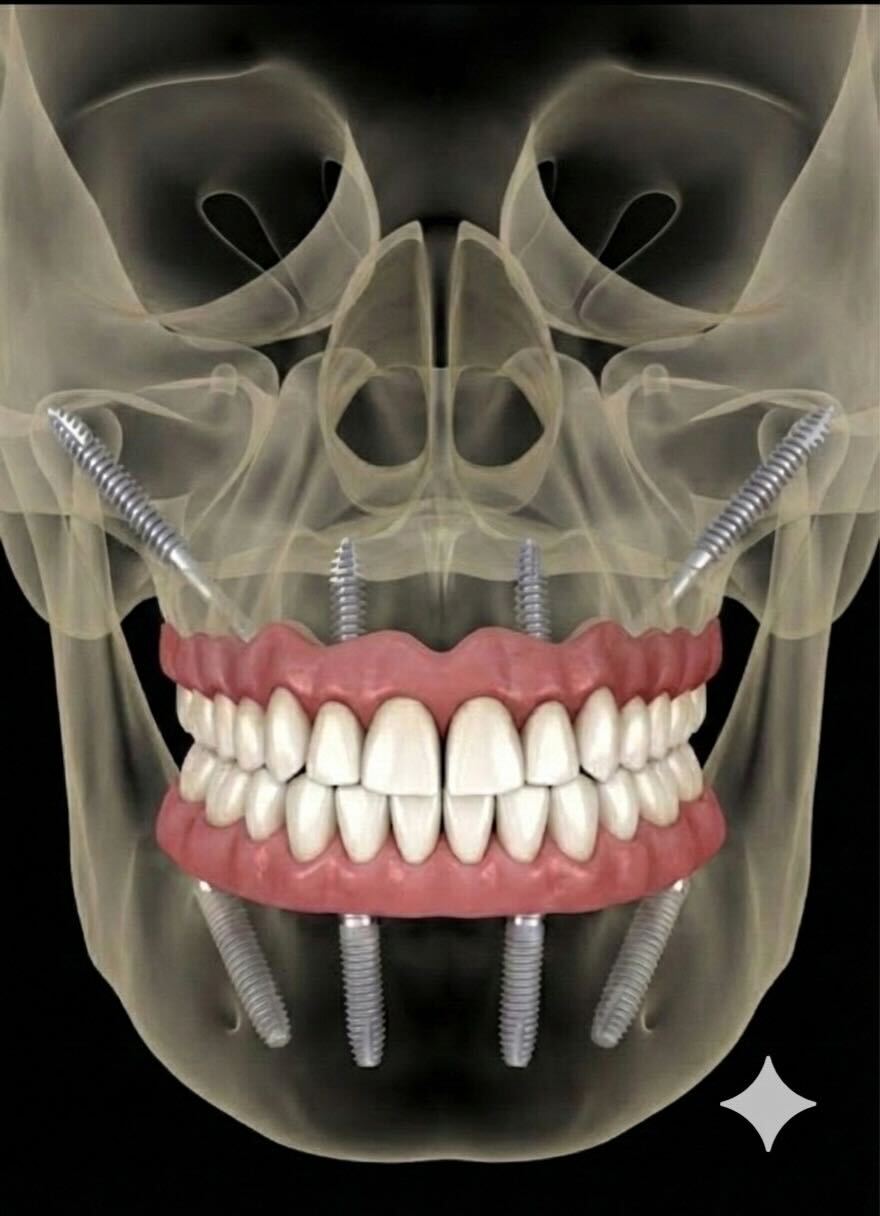

※ザイゴマインプラント:上顎の骨が極めて少ない難症例に対し、頬の骨(ザイゴマ)を支えに長いインプラントを埋入する特殊な治療法。骨移植が不要で、手術当日に固定式の仮歯を入れられるので、すぐに食事することが可能。

そうです。オールオン4やザイゴマインプラントは、「今ある骨の中で、どこが一番硬く信頼できるか」という発想で治療を組み立てます。

たとえば家を建てるとき、柔らかい土の上に基礎をつくることはありません。必ず、地盤の硬い層まで杭を打ち込みます。インプラントも同じ考え方です。

ザイゴマインプラントでは、上顎奥にある頬骨という非常に硬い骨を支点として利用します。これにより、通常のインプラントでは難しいとされる症例でも、しっかりとした固定を得られる可能性が広がります。オールオン4やザイゴマインプラントの手術直後は、腫れや痛み、違和感、出血などが発生する場合がありますが、大体2~3日で治まります。